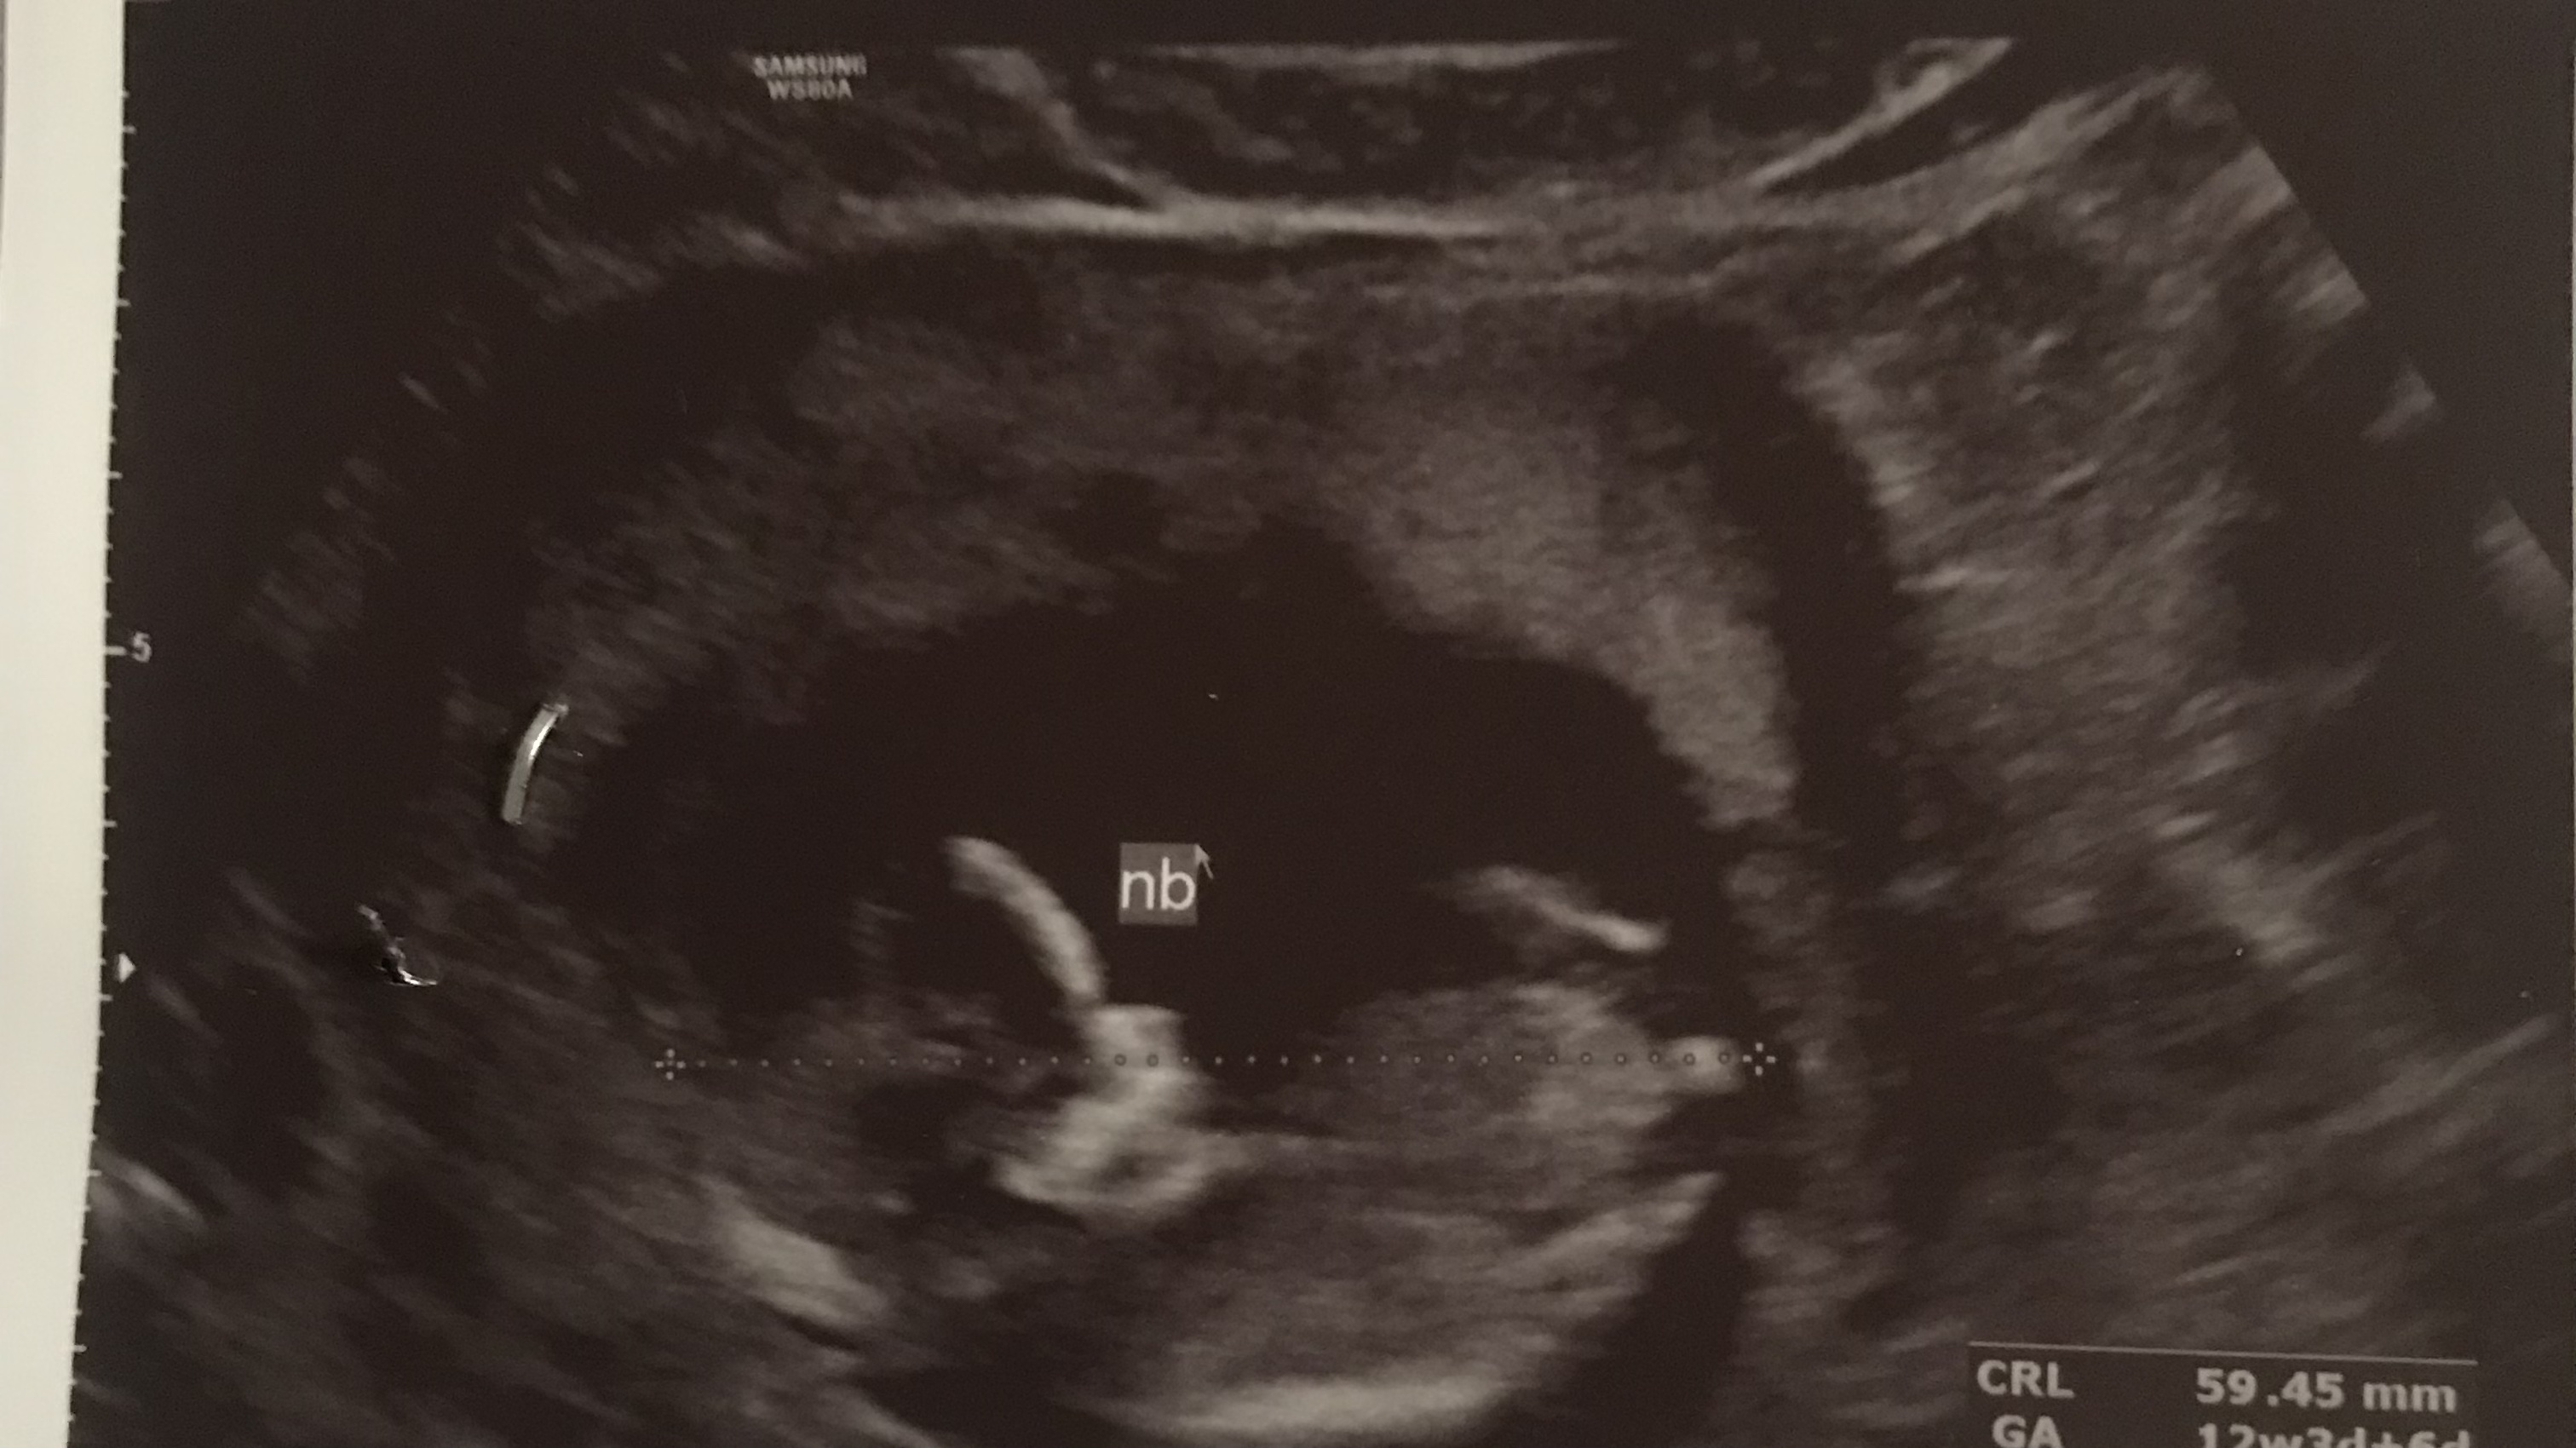

تعداد رای : 5

نظرسنجی

پسر

2

40%

دختر

3

60%